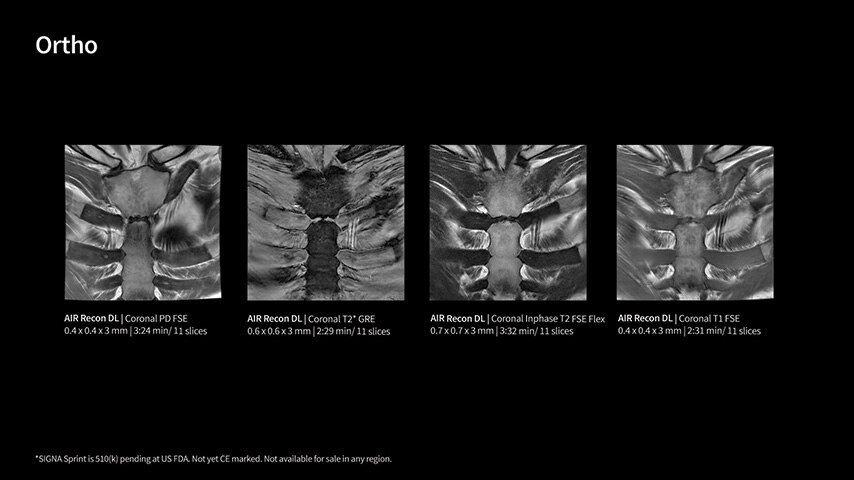

With GE HealthCare's comprehensive suite of deep-learning solutions integrated into SIGNA Sprint, you can unlock the full potential of your MRI system. No need for complicated patient setups or imaging protocols. The exceptional intelligence of our AI solutions offer multiple benefits, with AIR Recon DL giving pin-sharp images, Sonic DL accelerating scans up to 12x, and AIR x enabling automated slice placement. All helping to enhance your department’s workflow efficiency, increase patient throughput, and get the diagnostic clarity you need, faster.¹ Meaning you can spend more time on what truly matters—personalized patient care, enabling optimized treatment plans and treatment response monitoring—ultimately, supporting better clinical outcomes.